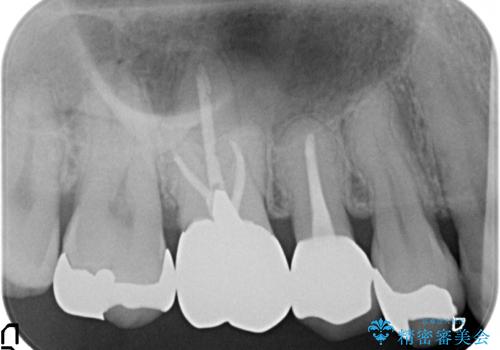

- 右上5番目の歯がなにもしなくてもズキズキ痛むので診て欲しいといらっしゃった方の症例です。

診査の結果神経を保存するのは困難だったため、根管治療を行った後、オールセラミッククラウンによる補綴を行いました。